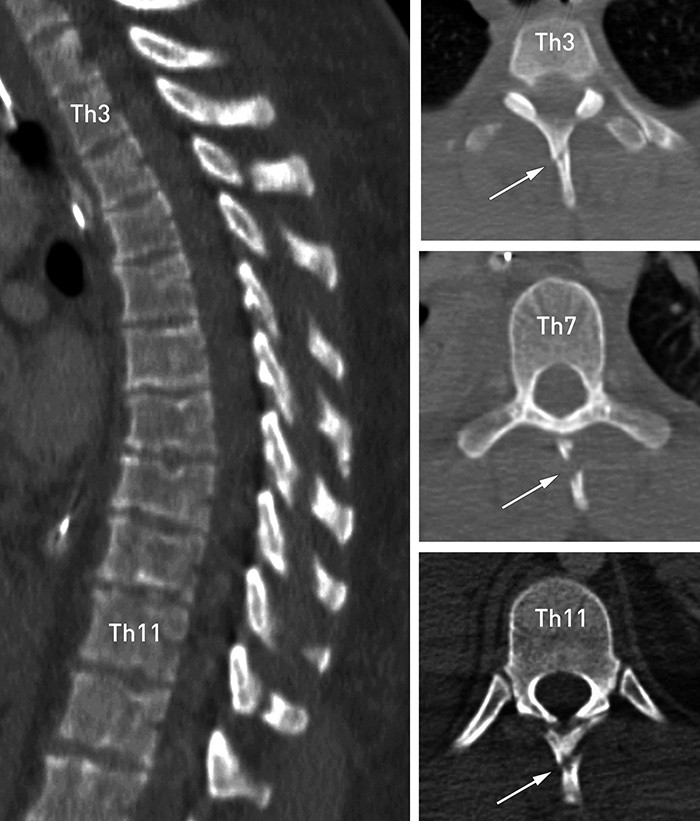

A man in his twenties incurred multiple injuries in a snowmobile accident. When examined at A&E he scored 9 on the Glasgow Coma Scale (GCS 9), had severe pain and tenderness over the thoracic column, but no focal neurological deficit. A trauma CT revealed cerebral haemorrhagic contusion, fractures in the skull base, shoulder blades and ribs and pneumothorax as a result of rib fractures. Nine isolated fractures of the spinous process, also called 'clay-shoveller's fractures', were also found, from Th3 to Th11. Clinical examination and image diagnostics did not raise suspicion of further damage to the column. The fractures of the spinal column were treated conservatively with pain-killers and immobilisation for six weeks. After that he was fully mobilised and free of pain.

Clay-shoveller's fracture is an occupational injury that received a great deal of attention in the 1930s when it occurred during construction work on motorways, in Germany, among other places (1). The fractures occurred in road workers who shovelled heavy loads. This type of fracture is relatively uncommon today, and is probably a frequently overlooked injury that is mainly associated with traffic accidents. Multilevel fractures (>  5) are very rare, and to our knowledge only two cases have been reported previously in the literature (2). Fractures may occur as a result of a direct blow to the spinous process or as a result of indirect trauma. A ballistic movement with strong extension, flexion or rotation of the cervicothoracic column may result in tearing of the supraspinous ligament. The fracture is usually stable and not associated with neurological deficit (1, 2). However, other injuries to the column must be excluded. The injury is normally treated conservatively (1, 2), but in some cases surgical extirpation of bone fragments is required for pain relief.